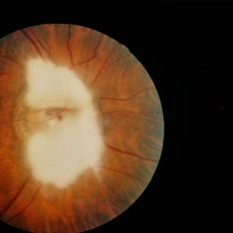

---thumb.jpg/image-square;max$300,300.ImageHandler) Myelinated Nerve Fiber

Myelinated Nerve Fiber

Feb 20 2013 by From the Collections of Thomas M. Aaberg, MD and Thomas M. Aaberg Jr., MD

Photo of an eye with myelinated nerve fiber around the optic nerve taken with a filter to show pseudofluorescence.

Condition/keywords: myelinated nerve fibers, pseudofluorescence